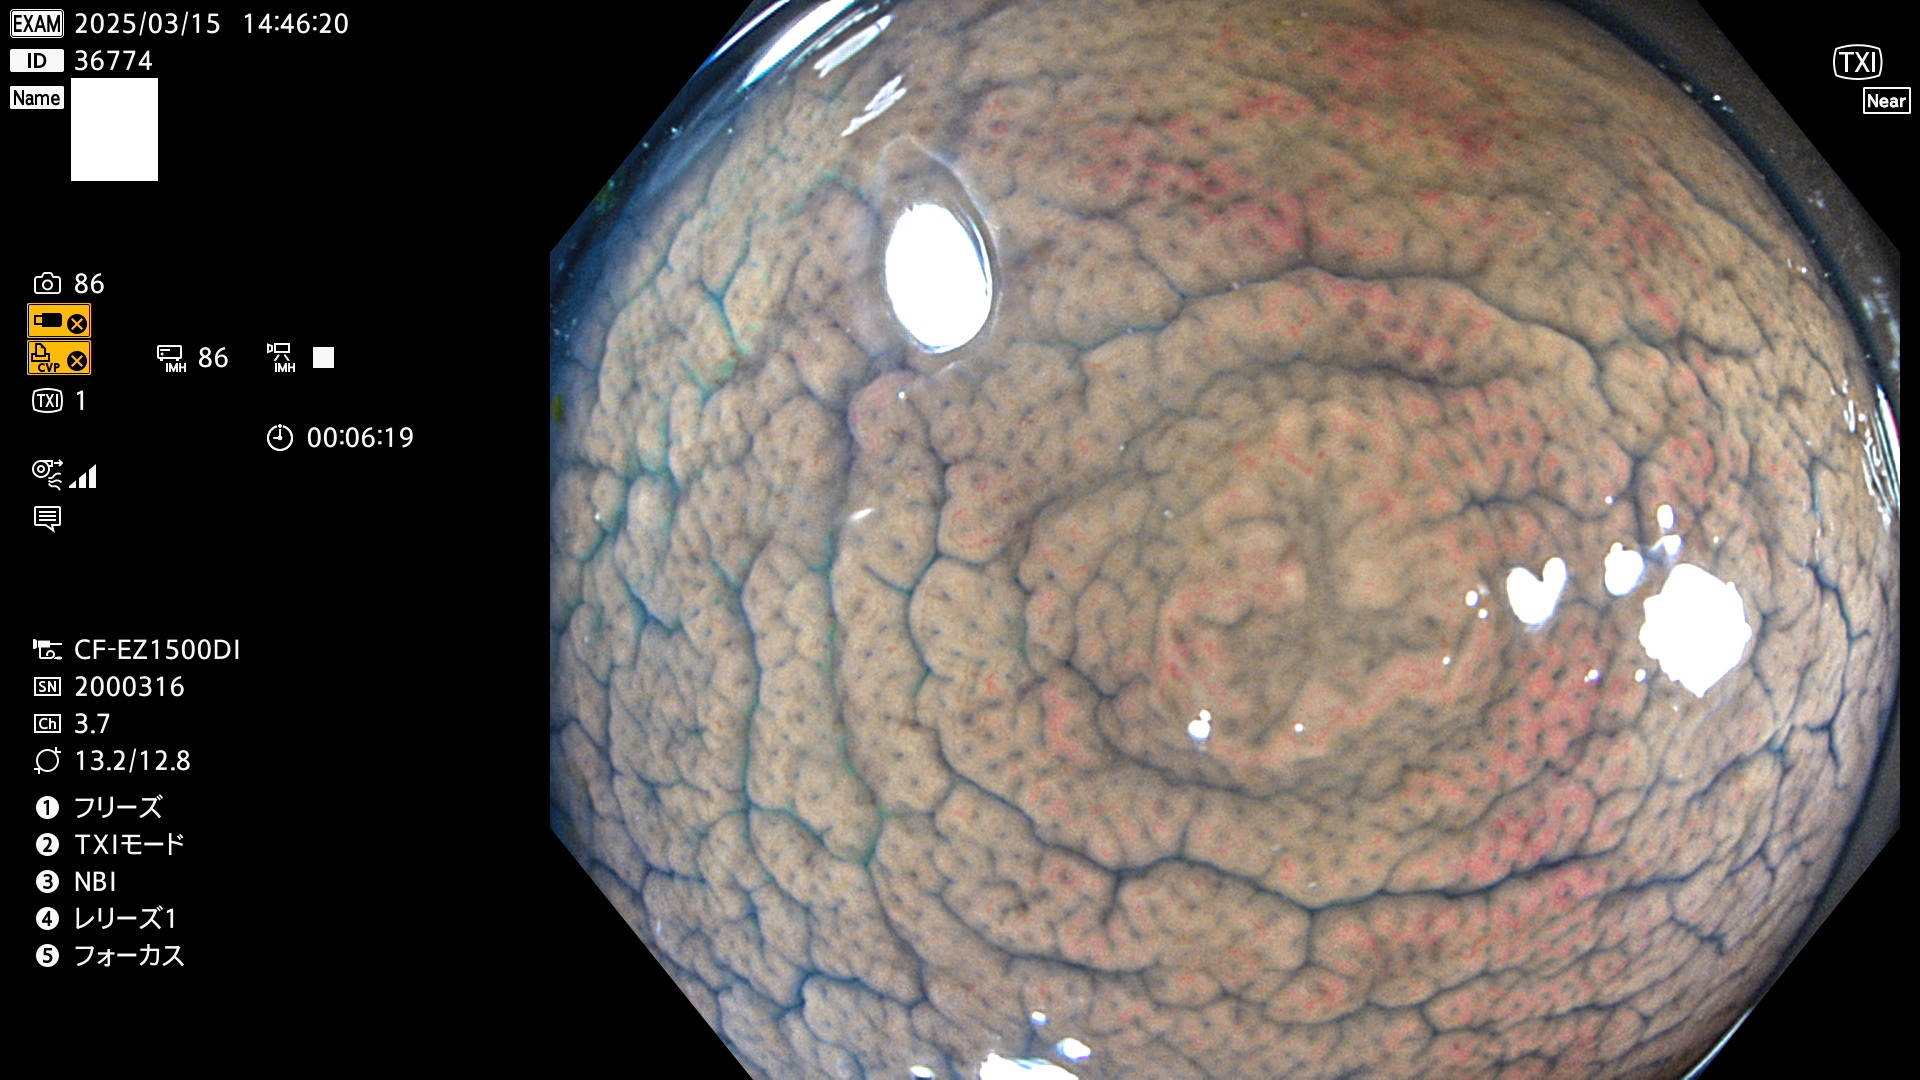

完全に平坦な物をUb、陥凹している物をUcと呼びます。最も発見が難しく危険な病変です。

毎週の検査(木・金・土・日)に発見されたUb、Uc型・腺腫を、その週の日曜の夜にUPし1週間、提示します。

抽出の対象期間 2025年3月13日〜3月16日の4日間(48件の検査)12個 (12/48=25%)